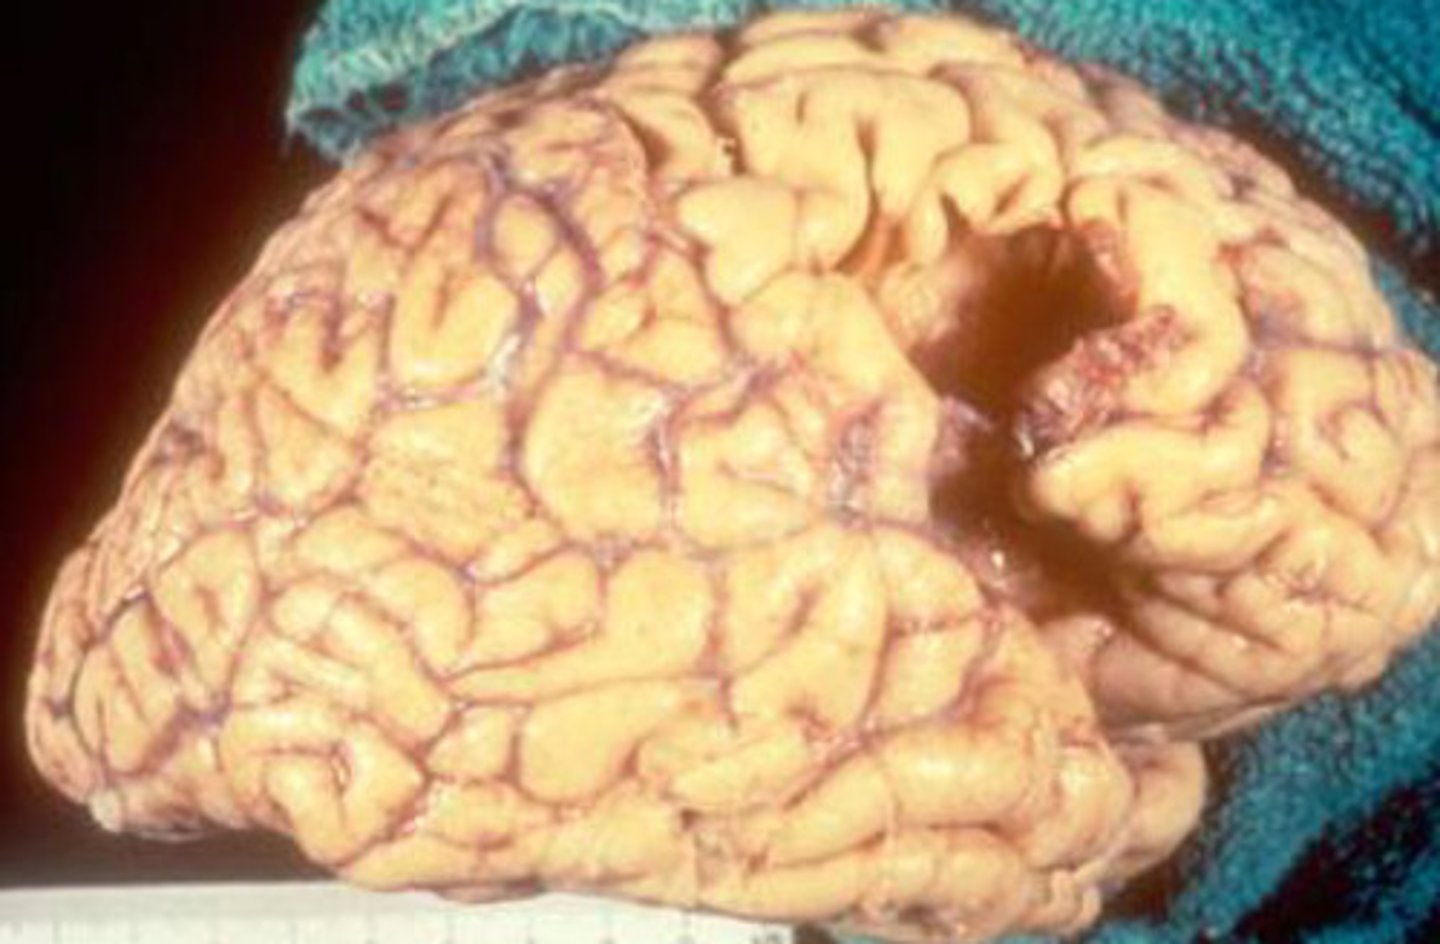

Liquefactive necrosis of the brain

What kind of necrosis is shown?